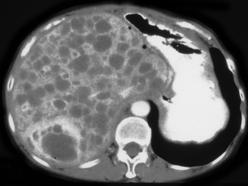

男,36岁,上腹部胀痛,CT检查如图所示,最可能的诊断是 ( )A、肝脓肿B、肝囊虫病C、肝癌D、多囊肝E、肝转移癌

问题 男,36岁,上腹部胀痛,CT检查如图所示,最可能的诊断是 ( )

选项 A、肝脓肿 B、肝囊虫病 C、肝癌 D、多囊肝 E、肝转移癌

答案 D